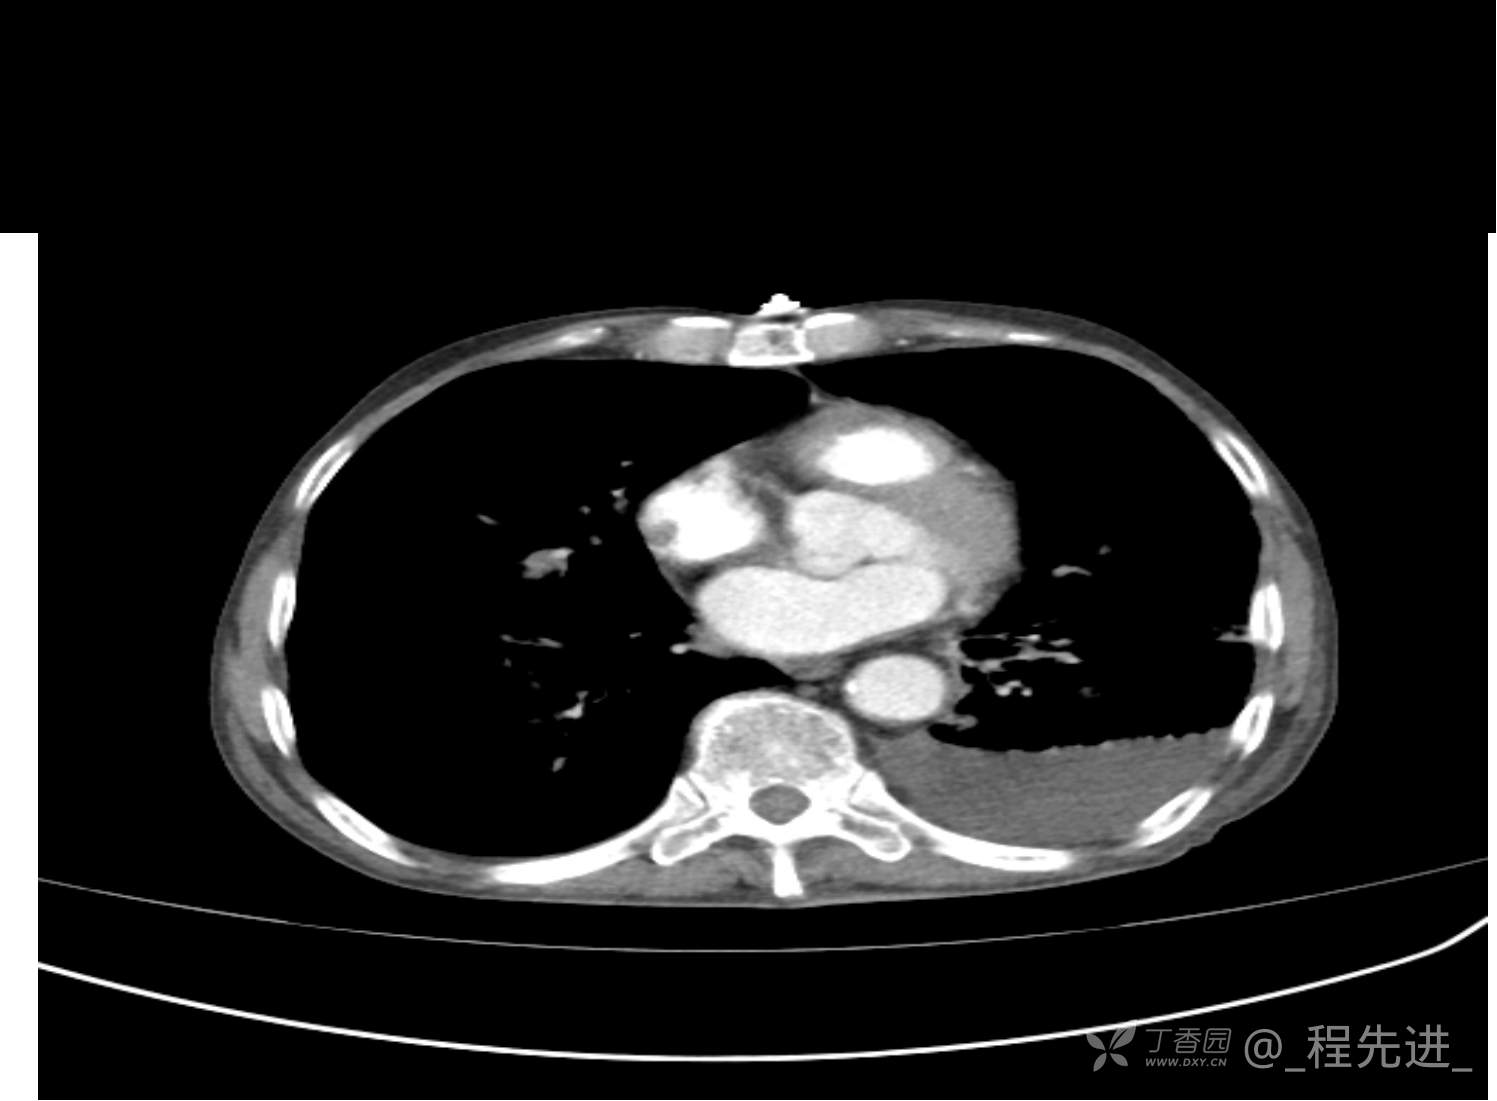

患者性别:男

患者年龄:81岁

简要病史:反复咳嗽、咳痰20余年,加重1周。两肺呼吸音低,可闻及散在干湿啰音。